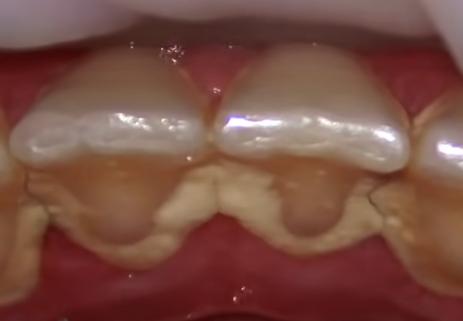

유해한 구강 박테리아는 치아를 덮고 있는 끈적끈적하고 투명한 막인 플라그를 생성합니다. 양치질과 치실 사용으로 플라그를 제거할 수 있지만 열악한 식습관과 구강 위생으로 인해 플라그가 남아 시간이 지남에 따라 축적될 수 있습니다.

결국 플라그가 굳어 치석이 됩니다. 치석의 축적은 충치와 잇몸 질환의 주요 요인입니다. 박테리아 및 기타 구강 미생물이 정착하여 치아와 잇몸에 감염을 일으킬 수 있는 쉬운 장소를 제공할 수 있습니다.

스케일링 및 루트 플래닝은 치아에서 치석을 제거합니다. 또한 잇몸이 다시 붙을 수 있도록 치아 뿌리의 거친 표면을 매끄럽게 합니다. 이를 통해 더 쉽게 구강 위생을 관리하고 치아와 잇몸의 추가 손상을 예방할 수 있습니다.